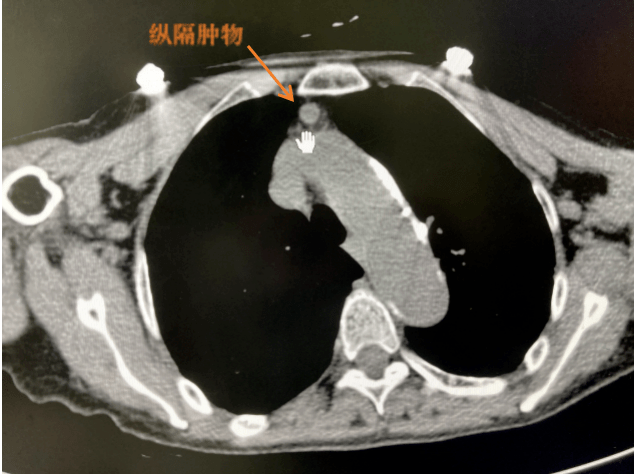

胸口纵膈肿瘤

陈女士在一次意外事故中摔倒,当地医院ct检查提示纵隔占位(肿瘤),因